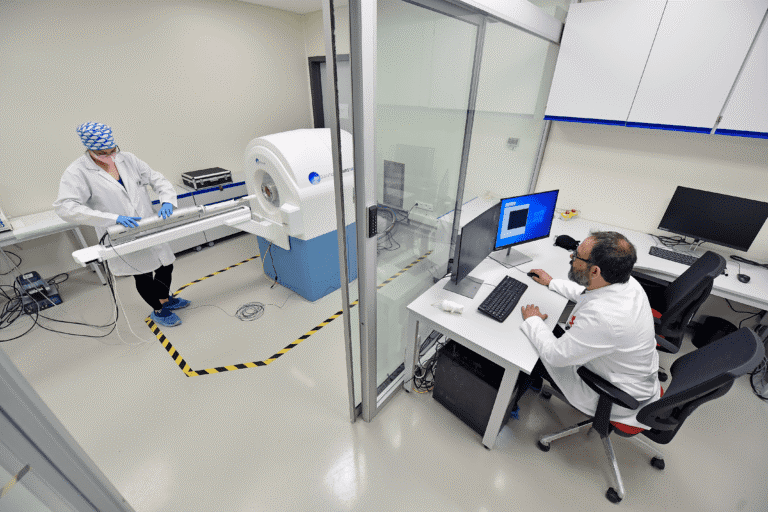

Preklinik Görüntüleme Birimimiz, kemirgen modellerde (sıçan ve fare) yüksek çözünürlüklü anatomik ve fonksiyonel görüntüleme imkânı sunmaktadır. 7T manyetik rezonans (MR) ve PET/BT cihazlarıyla donatılan altyapımız, hem akademik hem de endüstriyel araştırmalarda ileri düzey preklinik görüntüleme ihtiyaçlarını karşılamak üzere tasarlanmıştır.

Hedefli Tedavi Teknolojileri Merkezi Deney Hayvanları Görüntüleme Birimi’nde, MRSolutions MRS*DRYMAG 7017 7T (Tesla) preklinik deney hayvanı görüntüleme MRG tarayıcısı bulunmaktadır. Sistem in-vivo (canlı), ex-vivo (doku örnekleri) ve diğer (örneğin cihazlar, kimyasal bileşenler) görüntülemeler için uygundur.